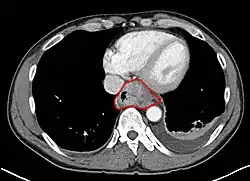

Anatomy

- Length is about 25 cm. Esophageal lesion distance on EGD is typically given from incisors

- Clinically important distance is from incisors to GEJ, which is ~40 cm.

- AJCC divisions of the esophagus: (These are based on adjacent surgical landmarks)

- Lower thoracic esophagus and EG junction:

- Inferior pulmonary veins to the stomach; includes the intraabdominal portion of the esophagus

- By endoscopy, 30 to 40 cm